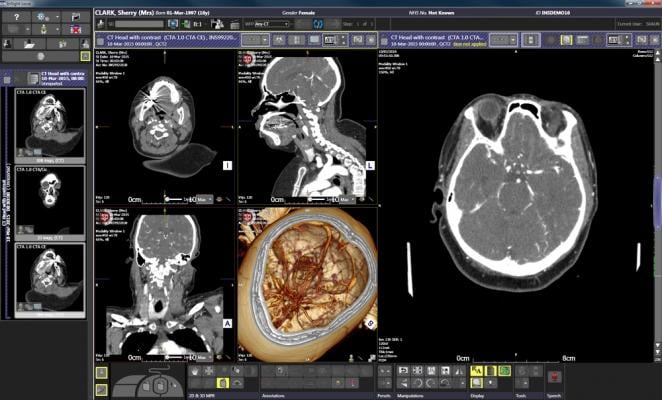

Medexprim’s Radiomics Enabler is an Extract/Transform/Load (ETL) solution. The software automates the selection, extraction, pseudonymization/de-identification and secured routing of larger numbers of image sequences from a picture archiving and communication system (PACS) for secondary use in research.

The combined solutions from Illuminate and Medexprim allow researchers to instantly create patient groups through data-mining of unstructured data from a variety of systems (EMR, RIS, LIS), extract corresponding reports and imaging exams, curate and pseudonymize the results. The cleansed contextualized data can then be accessed by data scientists and other researchers interested in finding correlations between imaging features and other phenotypes and/or genotypes, as well as developing training data sets for machine learning algorithms.

Researchers will also be able to streamline the process of collecting data in clinical trials involving medical imaging, with faster, more qualitative results. Alerts on new events on a cohort of patients configured by Illuminate automatically triggers the extraction of corresponding imaging exams, while automated quality and control and pseudonymization is supplied by the Medexprim solution.